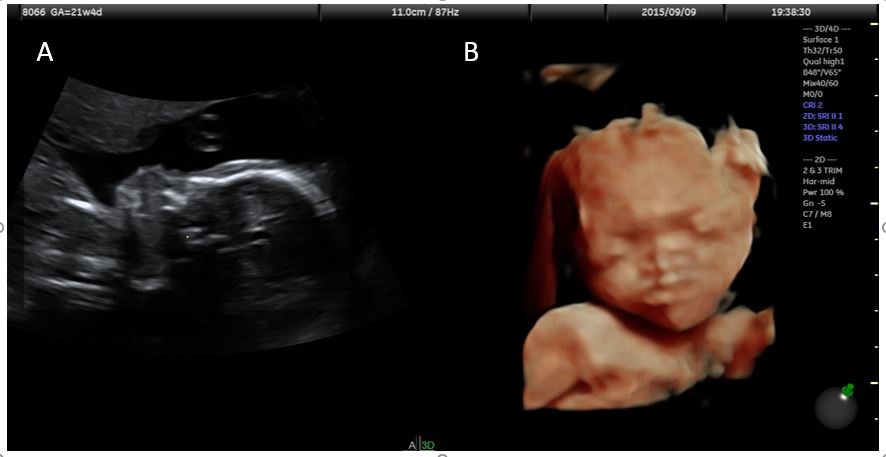

A 43-year old woman with 1 previous healthy child and a low-risk first-trimester screening test in the index pregnancy, presented at 21+4 weeks for routine second-trimester scan. At examination, a present (length 5.8 mm) but verticalized nasal bone was observed, resulting in a flat facial profile with underbite (Figures 1 and 2). No other major defects were detected and fetal biometry was observed. The couple were counselled about the tentative diagnosis of Binder syndrome, its potential implications and the limitations of prenatal diagnosis. Amniocentesis with array comparative hybridization (aCGH) was performed, indicating a normal female karyotype. At follow-up scans, no additional abnormalities were detected and the biometry of the long bones remained within normal limits. The course of pregnancy was uneventful, and an infant of 2750 g was born at 38+2 gestational weeks by elective caesarean section due to previous cesarean. At two months of life, the infant was doing well, and the only complaint at the time was tedious breathing and episodes of postprandial cough.

![A case of prenatally diagnosed Binder syndrome</br> [Apr 2017]](http://s834315022.websitehome.co.uk/wp-content/uploads/2020/11/cotm2017_apr-fig01a-b.jpg)